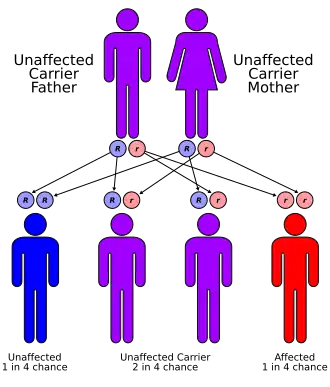

Fraser syndrome (also known as Meyer-Schwickerath's syndrome, Fraser-François syndrome, or Ullrich-Feichtiger syndrome) is an autosomal recessive congenital disorder,[1][2] identified by several developmental anomalies. Fraser syndrome is named for the geneticist George R. Fraser, who first described the syndrome in 1962.

The genetic background of this disease has been linked to a gene called FRAS1, which seems to be involved in skin epithelial morphogenesis during early development.[7] It has also been associated with FREM2[8] and with GRIP1.[9]